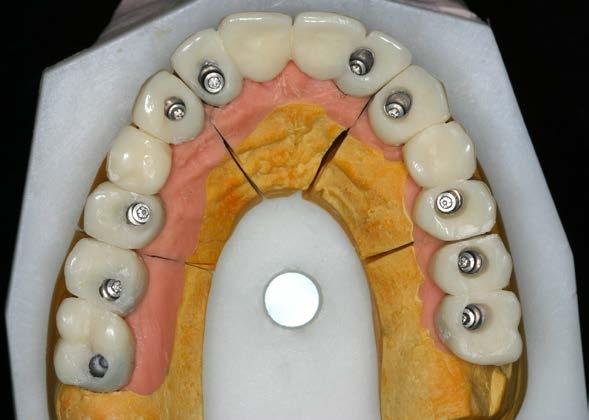

Seguimiento clínico a 25 años de una rehabilitación implantosoportada en una paciente joven con periodontitis de inicio temprano: reporte de caso

Seguimiento clínico a 25 años de una rehabilitación implantosoportada

Figura 4. Prótesis de carga progresiva finalizada, lista para su colocación.

5 y 6. Prótesis atornillada de carga progresiva en la fase previa a la confección de la prótesis definitiva.

En el arco superior se planifica una rehabilitación cementada por tramos, que en ese contexto representaba la mejor alternativa en términos de estética y estanqueidad, mediante pilares específicos para fresado. Para ello se programan 10 implantes. En una primera fase se realiza la carga inmediata

del sector anterior y la carga definitiva de los implantes mandibulares mediante una prótesis de resina atornillada (Figura 3).

Seis meses después se cargan los implantes de los sectores posteriores con una prótesis atornillada sobre transepiteliales de larga duración en metal-resina, lo que permite generar una carga controlada y favorecer la adecuada conformación de los tejidos periimplantarios (Figura 4).

Una vez alcanzada la estabilidad de los tejidos blandos, 6 meses después de la carga progresiva se inicia la confección de la prótesis definitiva (Figuras 5 y 6).

El diseño de la prótesis superior se basa en la confección de pilares de oro ceramizado en los sectores anteriores, con el objetivo de optimizar la estética, y biopilares fresables en la zona posterior. Estos pilares permiten una correcta adaptación al perfil gingival y presentan un adecuado grado de estanqueidad, minimizando el riesgo de microfiltraciones que puedan favorecer infecciones periimplantarias. Hace 25 años constituían una de las mejores alternativas estéticas y funcionales para este tipo de rehabilitaciones.